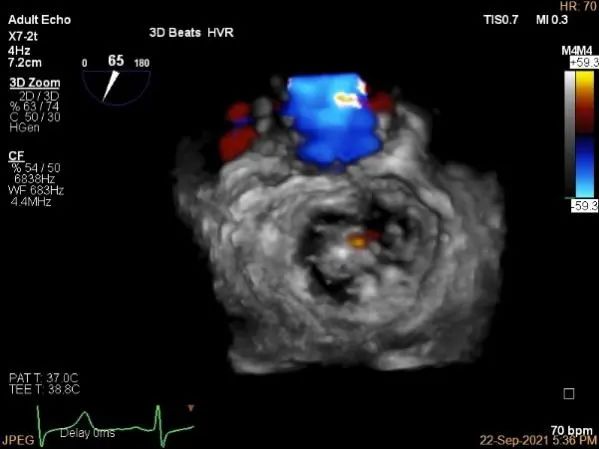

三维评估两个夹子位置

3D-color再次确定未见残余分流

评估瓣口条件,平均跨瓣压差:4mmHg

3D:P1区脱垂并腱索断裂,Width:11.4mm

3D-color:重度MR,4级

3d确认夹子位置在P1区

3d-color确认残余分流情况